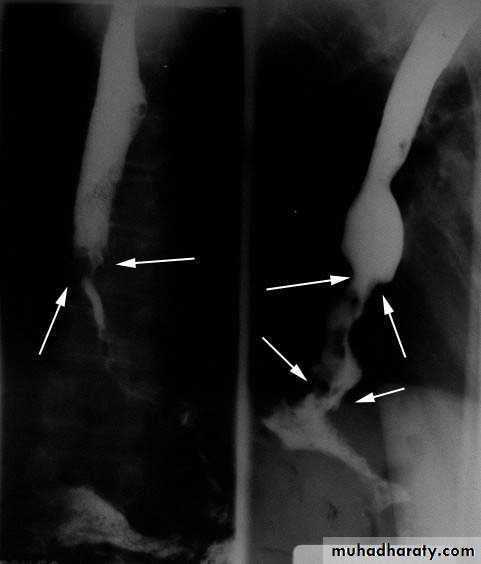

Esophageal Carcinoma

Esophageal cancer.

A, adenocaB, Sq cell ca.

Esophageal adenoca. Sq cell ca.

AdenocarcinomaCommonest type in US

Risk factor: Barrett esophagus

Distal 1/3 of esophagus

Symptoms: late obstruction

• Squamous cell carcinoma

• Commonest type worldwide

• Risk factors: smoking, alcohol, genetics, esophagitis.

• Middle 1/3 of esophagus

• Symptoms: insidious onset; late obstruction